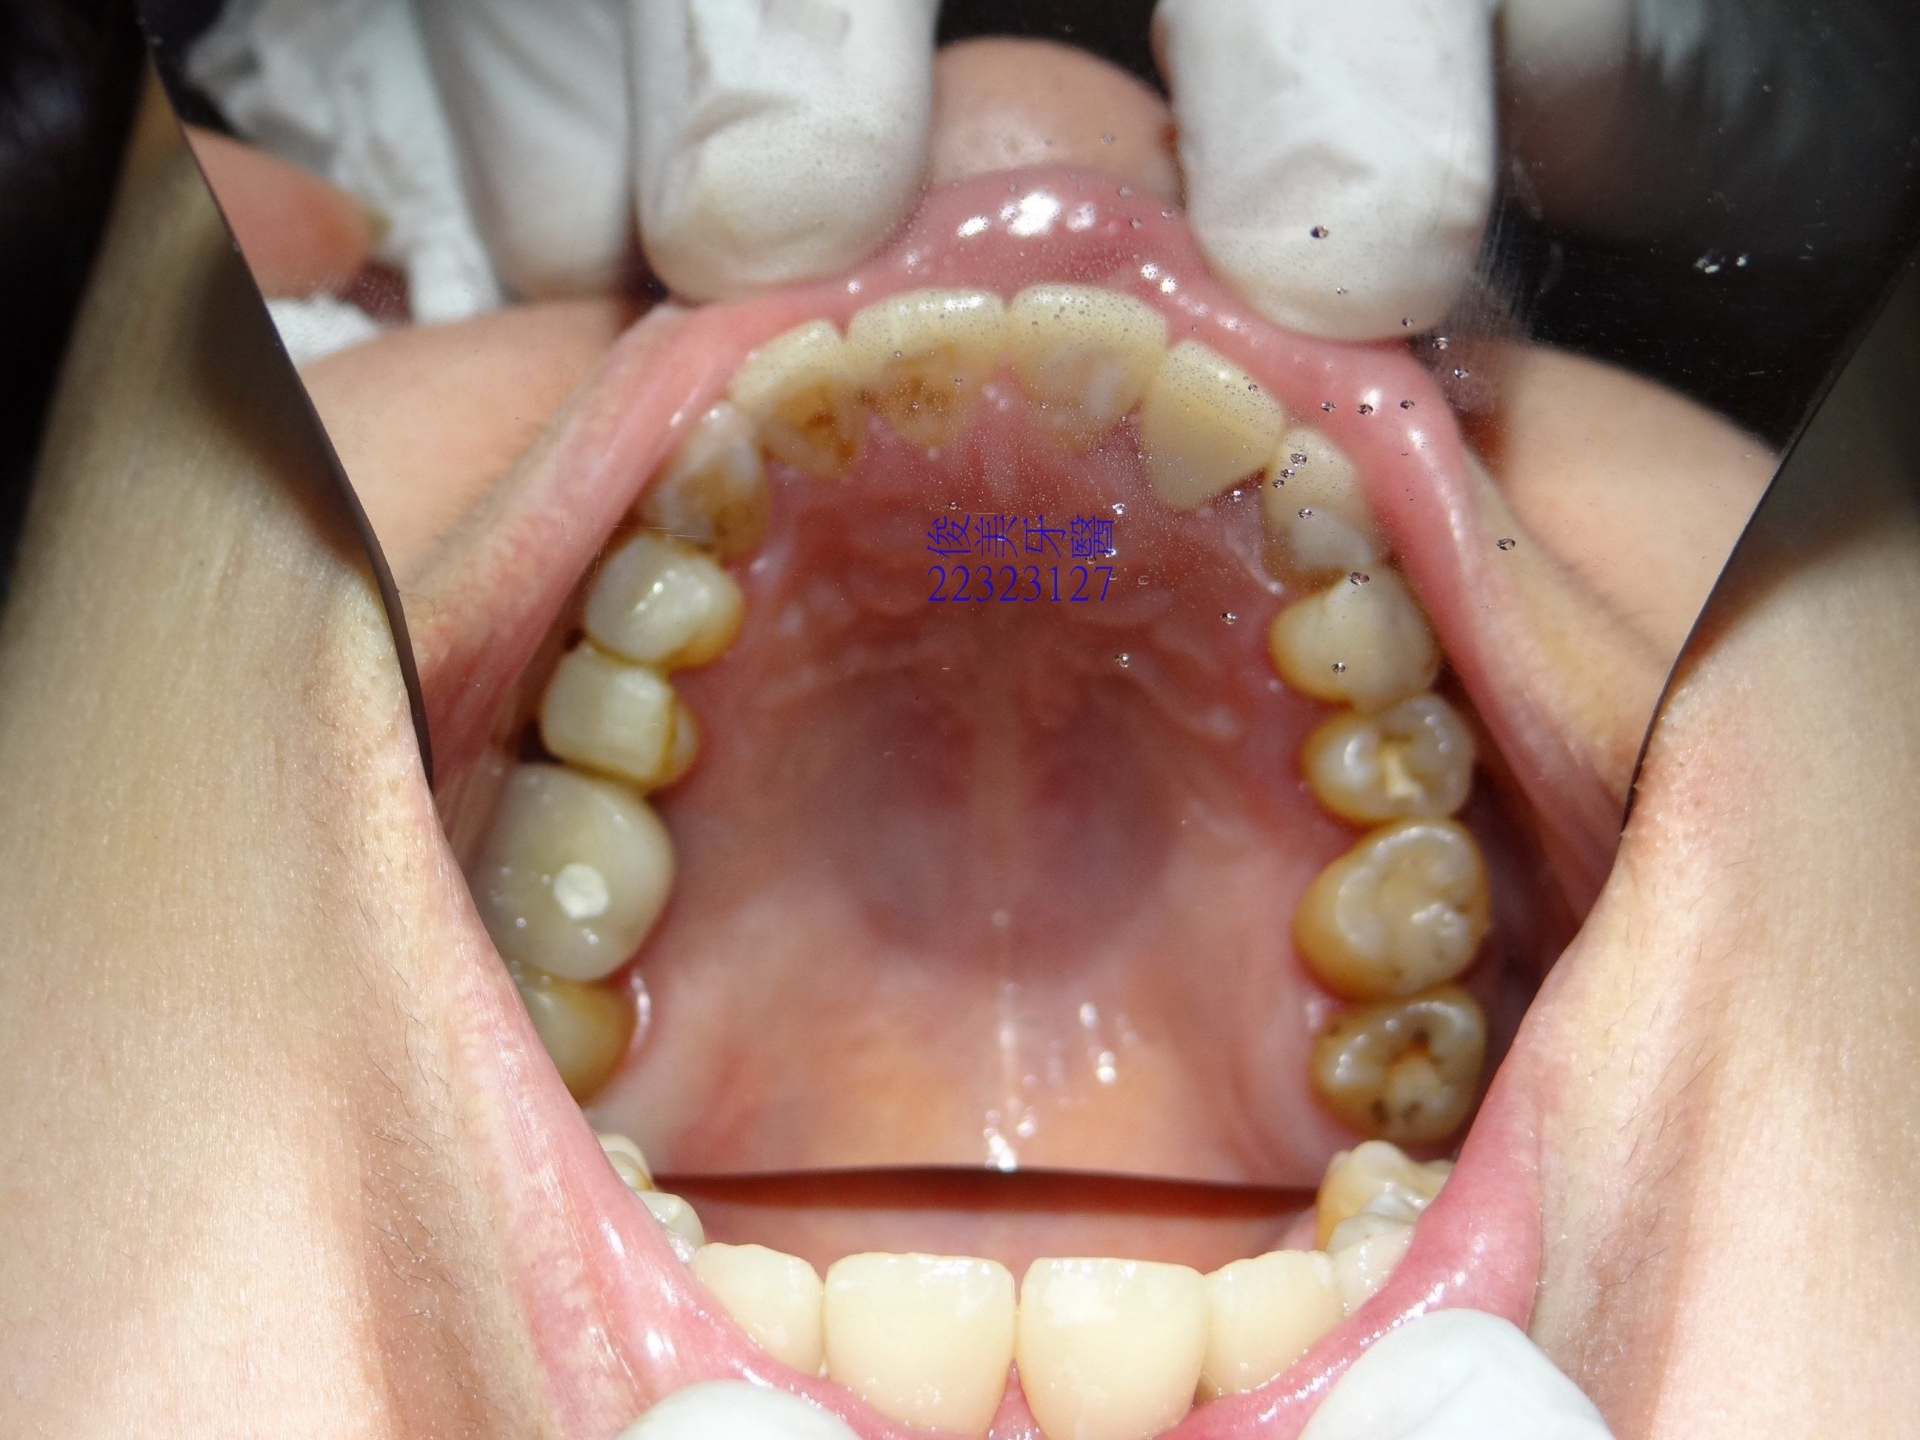

上顎狀況。